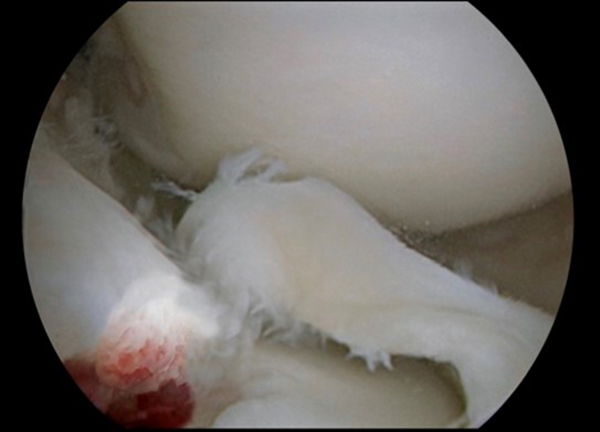

Se realizaron los portales habituales de rodilla: anteromedial y anterolateral, se evidenció lesión en asa de balde del menisco interno, luxada hacia intercóndilo asociada a fractura grado 3 de espina tibial (fig. 4).

Figura 4: Visión artroscópica de rodilla derecha. Fractura de espina tibial y asa de balde del menisco interno.